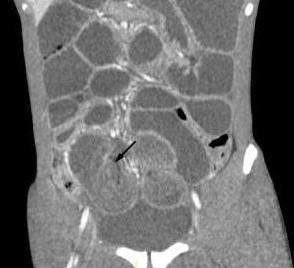

A CT scan of the abdominopelvic region was obtained to rule out bowel obstruction. An axial CT image showed significant distention of the distal ileal loops with concentric alternating rings of high and low attenuation and swirling of the mesenteric fat and mesenteric vessels (Figure 1, above). Figure 2 (left) shows the intussusceptum (arrows), with an accompanying complex of mesenteric fat and blood vessels, surrounded by the thick-walled intussuscipiens. Surgery was performed to prevent vascular compromise and bowel necrosis. Operative findings revealed ileal intussusception and intestinal necrosis secondary to an invaginated Meckel’s diverticulum. Postopertaively, the patient did well without any complications.

CT usually reveals a bowel-within-bowel configuration, with mesenteric fat and mesenteric vessels- a clinical picture pathognomonic for intussusception (Figure 2). CT imaging is useful in the diagnosis of intestinal obstruction, but it is not helpful in determining the cause of intussusception, because the lead point is often small and hidden within the intussusceptum.5